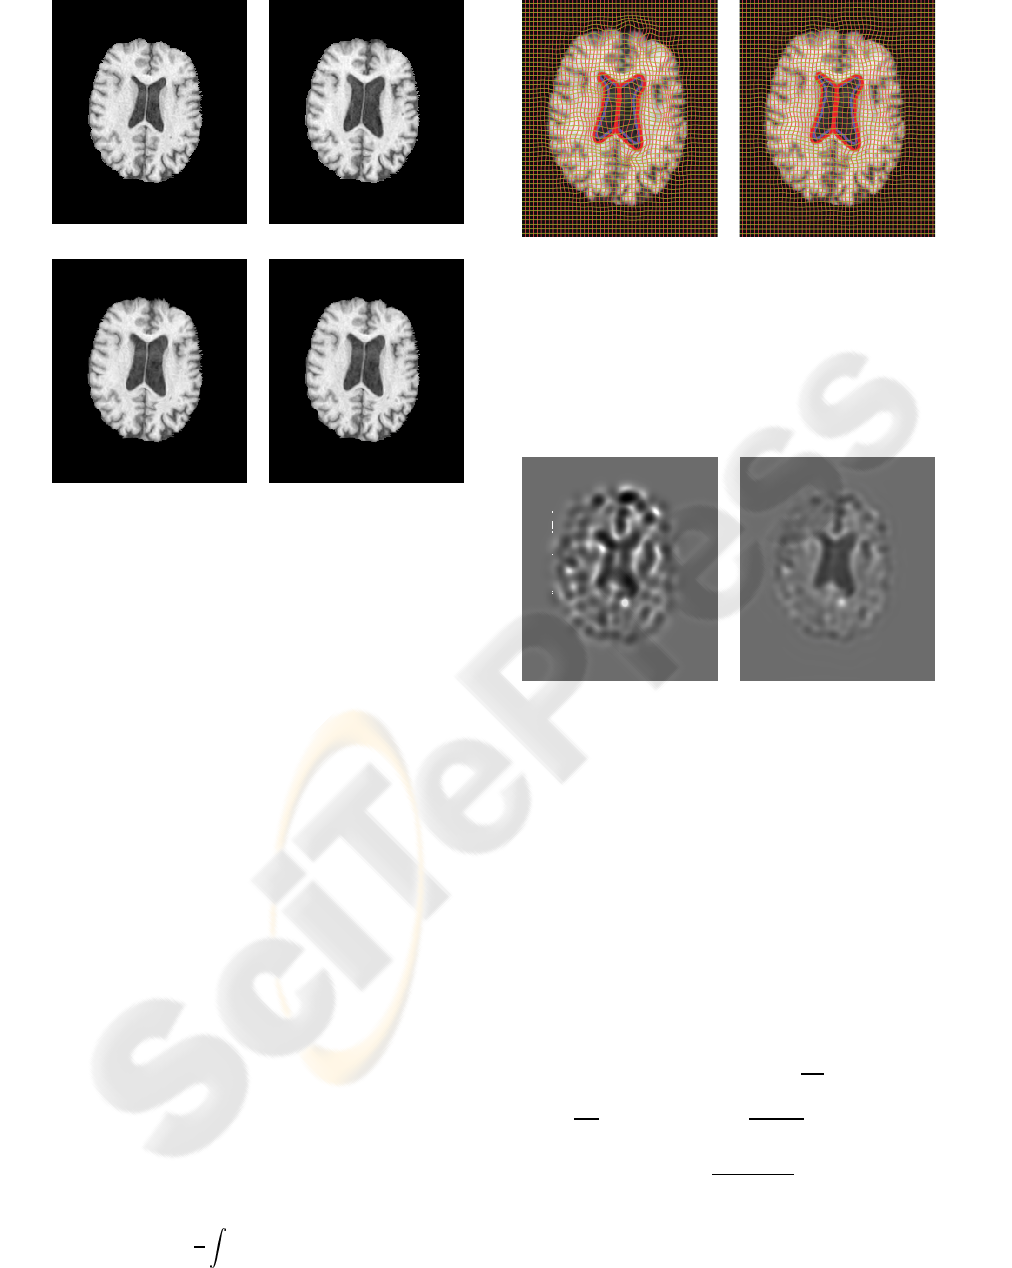

Figure 5: Serial MRI example. (a) image T; (b) image S; (c)

image T is deformed to image S using Christensen’s model;

(d) image T is deformed to image S using the proposed

model.

(a) (b)

Figure 6: Serial MRI example. Results obtained with (a)

Christensen’s model and (b) the proposed model. Blue, yel-

low and red contours represent the boundaries of ventricles

in T, S, and deformed T, respectively. Note that for both

methods, yellow contour is essentially invisible due to a

very close match. However, the resulting grid of the pro-

posed method is visually more regular.

Figure 7: Serial MRI example. Jacobian map of the defor-

mation using (a) Christensen’s model and (b) the proposed

In Figures 5 through 9, we show the results of

matching a pair of 2D slices from a set of Serial MRI

images (each of size 226 by 256; λ = 400 in (15)),

where visually significant ventricle enlargement is

present. Both Christensen’s method and the proposed

model generated a close match between the deformed

image and the study (Figure 5(a-d)). Here, there is no

reason to not evenly distribute Jacobian field inside

the ventricles, as realized using the proposed method.

In contrast, Christensen’s method generated a density

map with extreme values along the ventricular bound-

ary. Indeed, given the overall longitudinal ventricu-

lar dilatation, we argue that the corresponding density

change map should be constant inside the ventricle.

As seen in Figure 9, both the standard deviation inside

the ventricle and the symmetric KL distance increased

for Christensen’s method, while these quantities sta-

bilized for the proposed method.